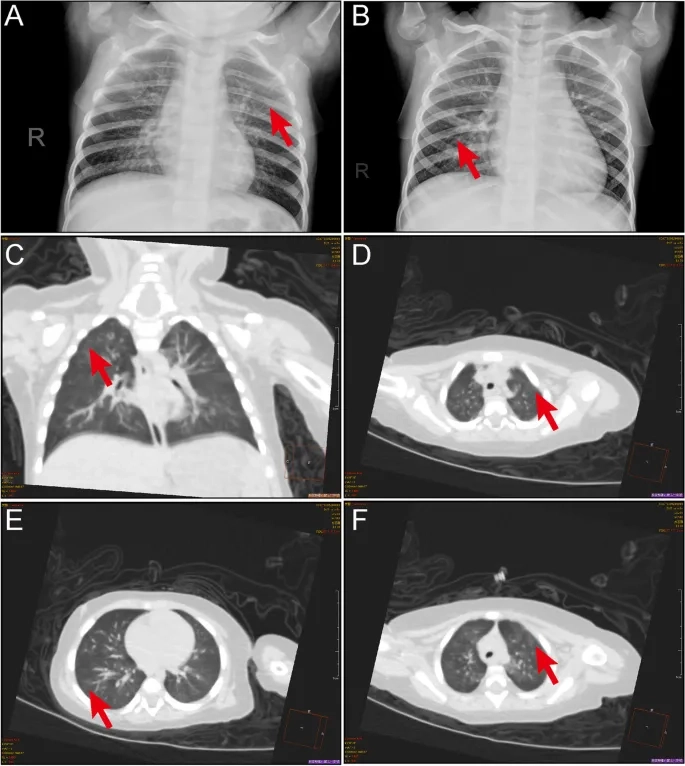

Images of Human Metapneumovirus Infection